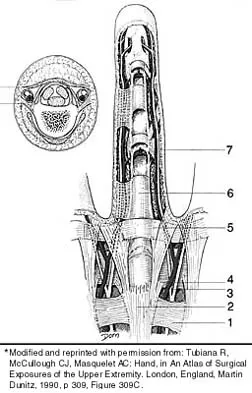

Which of the following anatomic structures is labeled 6 in Figure 27?

Explanation

The line labeled 6 points to the A2 pulley. This structure is the condensation of the digital flexor tendon sheath corresponding to the proximal aspect of the proximal phalanx. Grayson's ligament is volar to the digital nerve and artery. Cleland's ligament is dorsal to the digital nerve and artery. The sagittal band anchors the extensor tendons over the metacarpophalangeal joints. The triangular ligament connects the lateral bands just proximal to the terminal tendon inserting onto the base of the distal phalanx. Hollinshead WH: Anatomy for Surgeons: The Back and Limbs, ed 3. Philadelphia, PA, Harper and Row, 1982, p 467.

References:

- Tubiana R, McCullough CJ, Masquelet AC: An Atlas of Surgical Exposures of the Upper Extremity. Philadelphia, PA, JB Lippincott, 1990, p 309.